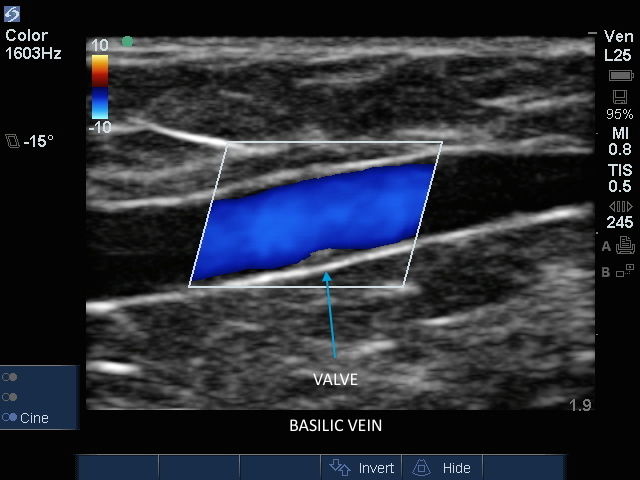

Imagen a color de la vena basílica con válvula